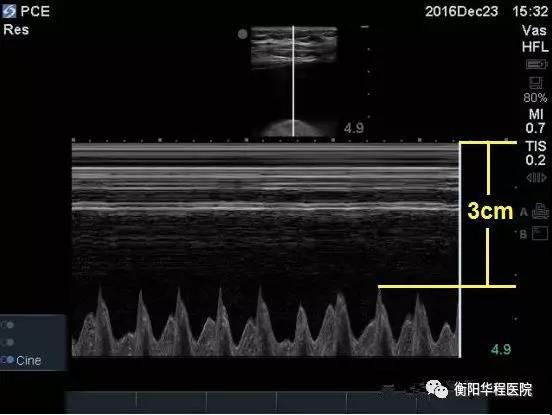

圖2 第5肋間M超可見舒張期心臟到胸壁皮膚距離約為3cm